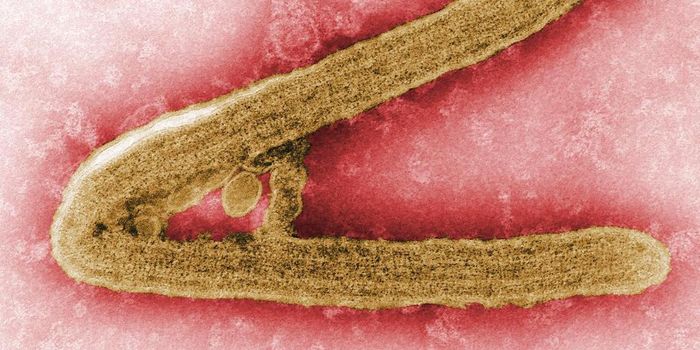

FEB 11, 2022MicrobiologyEbola virus has caused several major outbreaks in recent decades. Its high death rate and disturbing symptoms have made ...